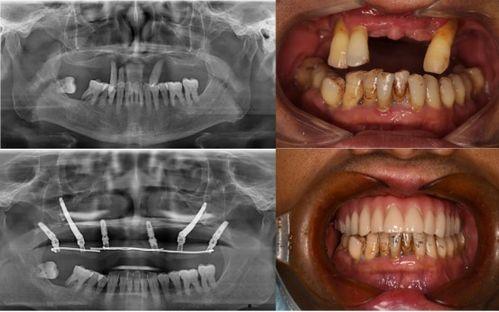

据患者们反映,他们在种植牙的过程中,遇到了种种问题。有的患者表示,医生在手术过程中操作不规范,导致种植牙失败;有的患者则抱怨,术后恢复期过长,而且效果并不理想。更有甚者,竟然出现了种植牙植入后,牙槽骨吸收的情况。